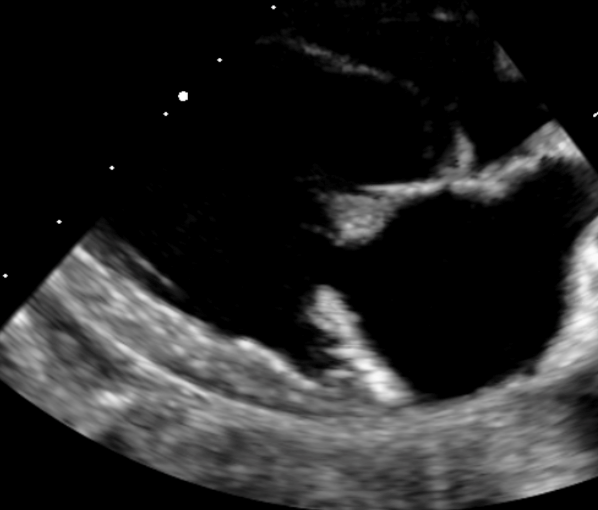

• Utiliser les anomalies observées en modes 2D, TM et Doppler pour classifier et graduer les cardiopathies acquises.

• Étude de cas interactifs à partir d’images fixes et de vidéos en échographie cardiaque (modes 2D, TM, Doppler).

• Principes de l’échocardiographie 2D, TM et Doppler appliqués aux cardiopathies acquises.